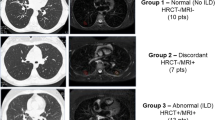

First, HRCT images were evaluated for suitability for the study, and non-eligible patients, according to the exclusion criteria, were excluded. Then, all HRCT images were evaluated according to the ILD staging system, which was described by Goh et al [29] (Supplementary; Fig. 1). Briefly, CT images were scored at five levels (the origin of great vessels, the main carina, the pulmonary venous confluence, halfway between the third and fifth sections, and immediately above the right hemidiaphragm) and the disease extent was estimated as a percentage of the total area to the nearest 5% in each of the five CT sections. The total extent of ILD (TEI) detected by HRCT was calculated as the mean extent score in the five scored CT sections. The TEI ≤ 10% was accepted as limited, and ≥ 30% was accepted as an extensive disease. For indeterminate cases (with the extent of ILD at 10–30%), FVC was considered as FVC ≥ 70% indicating limited disease and FVC < 70% indicating extensive disease [29]. We also calculated the modified coarseness of reticular disease (MCRD) in each of the five sections according to Goh et al [29] as follows: 0, normal; 1, ground-glass opacity alone; 2, fine intra-lobular fibrosis; 3, microcystic honeycombing (≤ 4 mm); 4, macrocystic honeycombing (> 4 mm). The highest score in each section was taken into account and the MCRD was the summed score for all five levels and MCRD accepted as ≤ 10 (mild reticulation) and > 10 (severe reticulation).